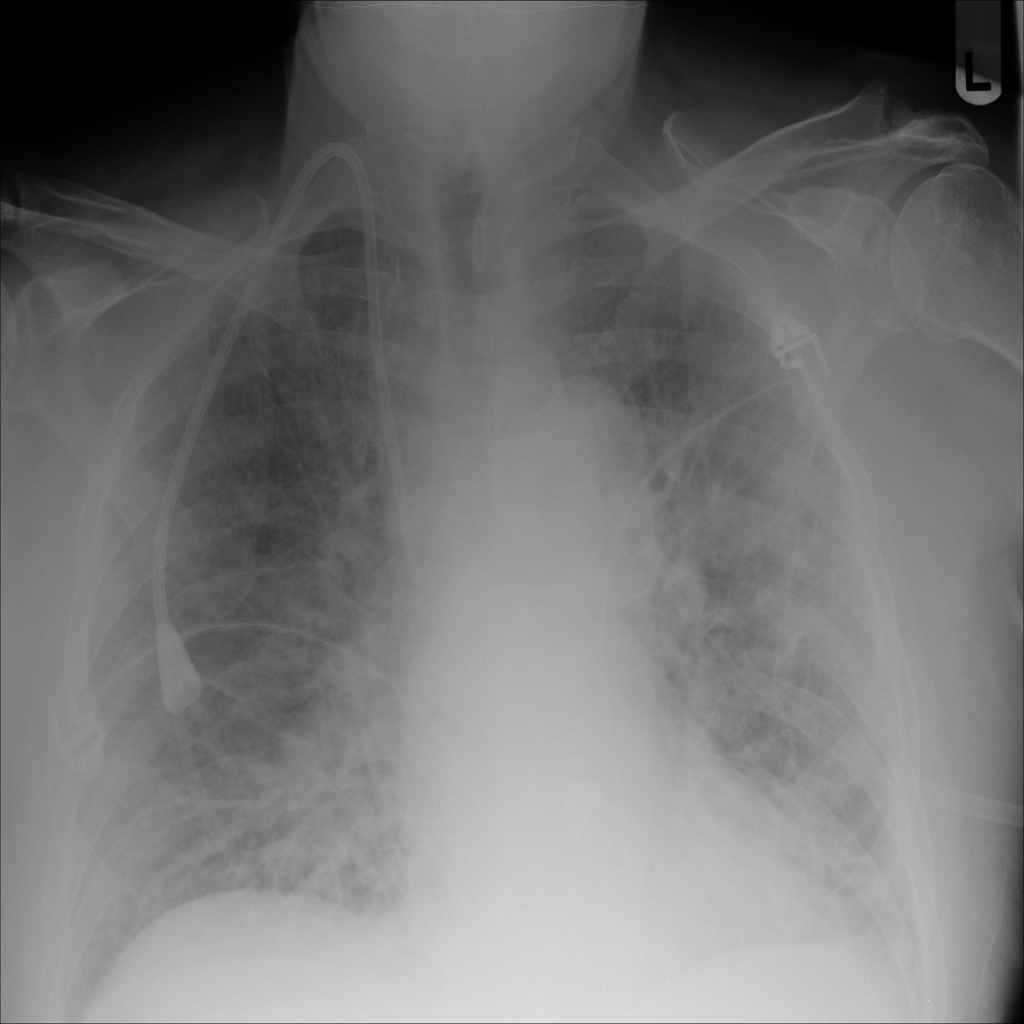

PAT-5B86 · IMG-009Edema

PAT-5B86 · IMG-009

PA